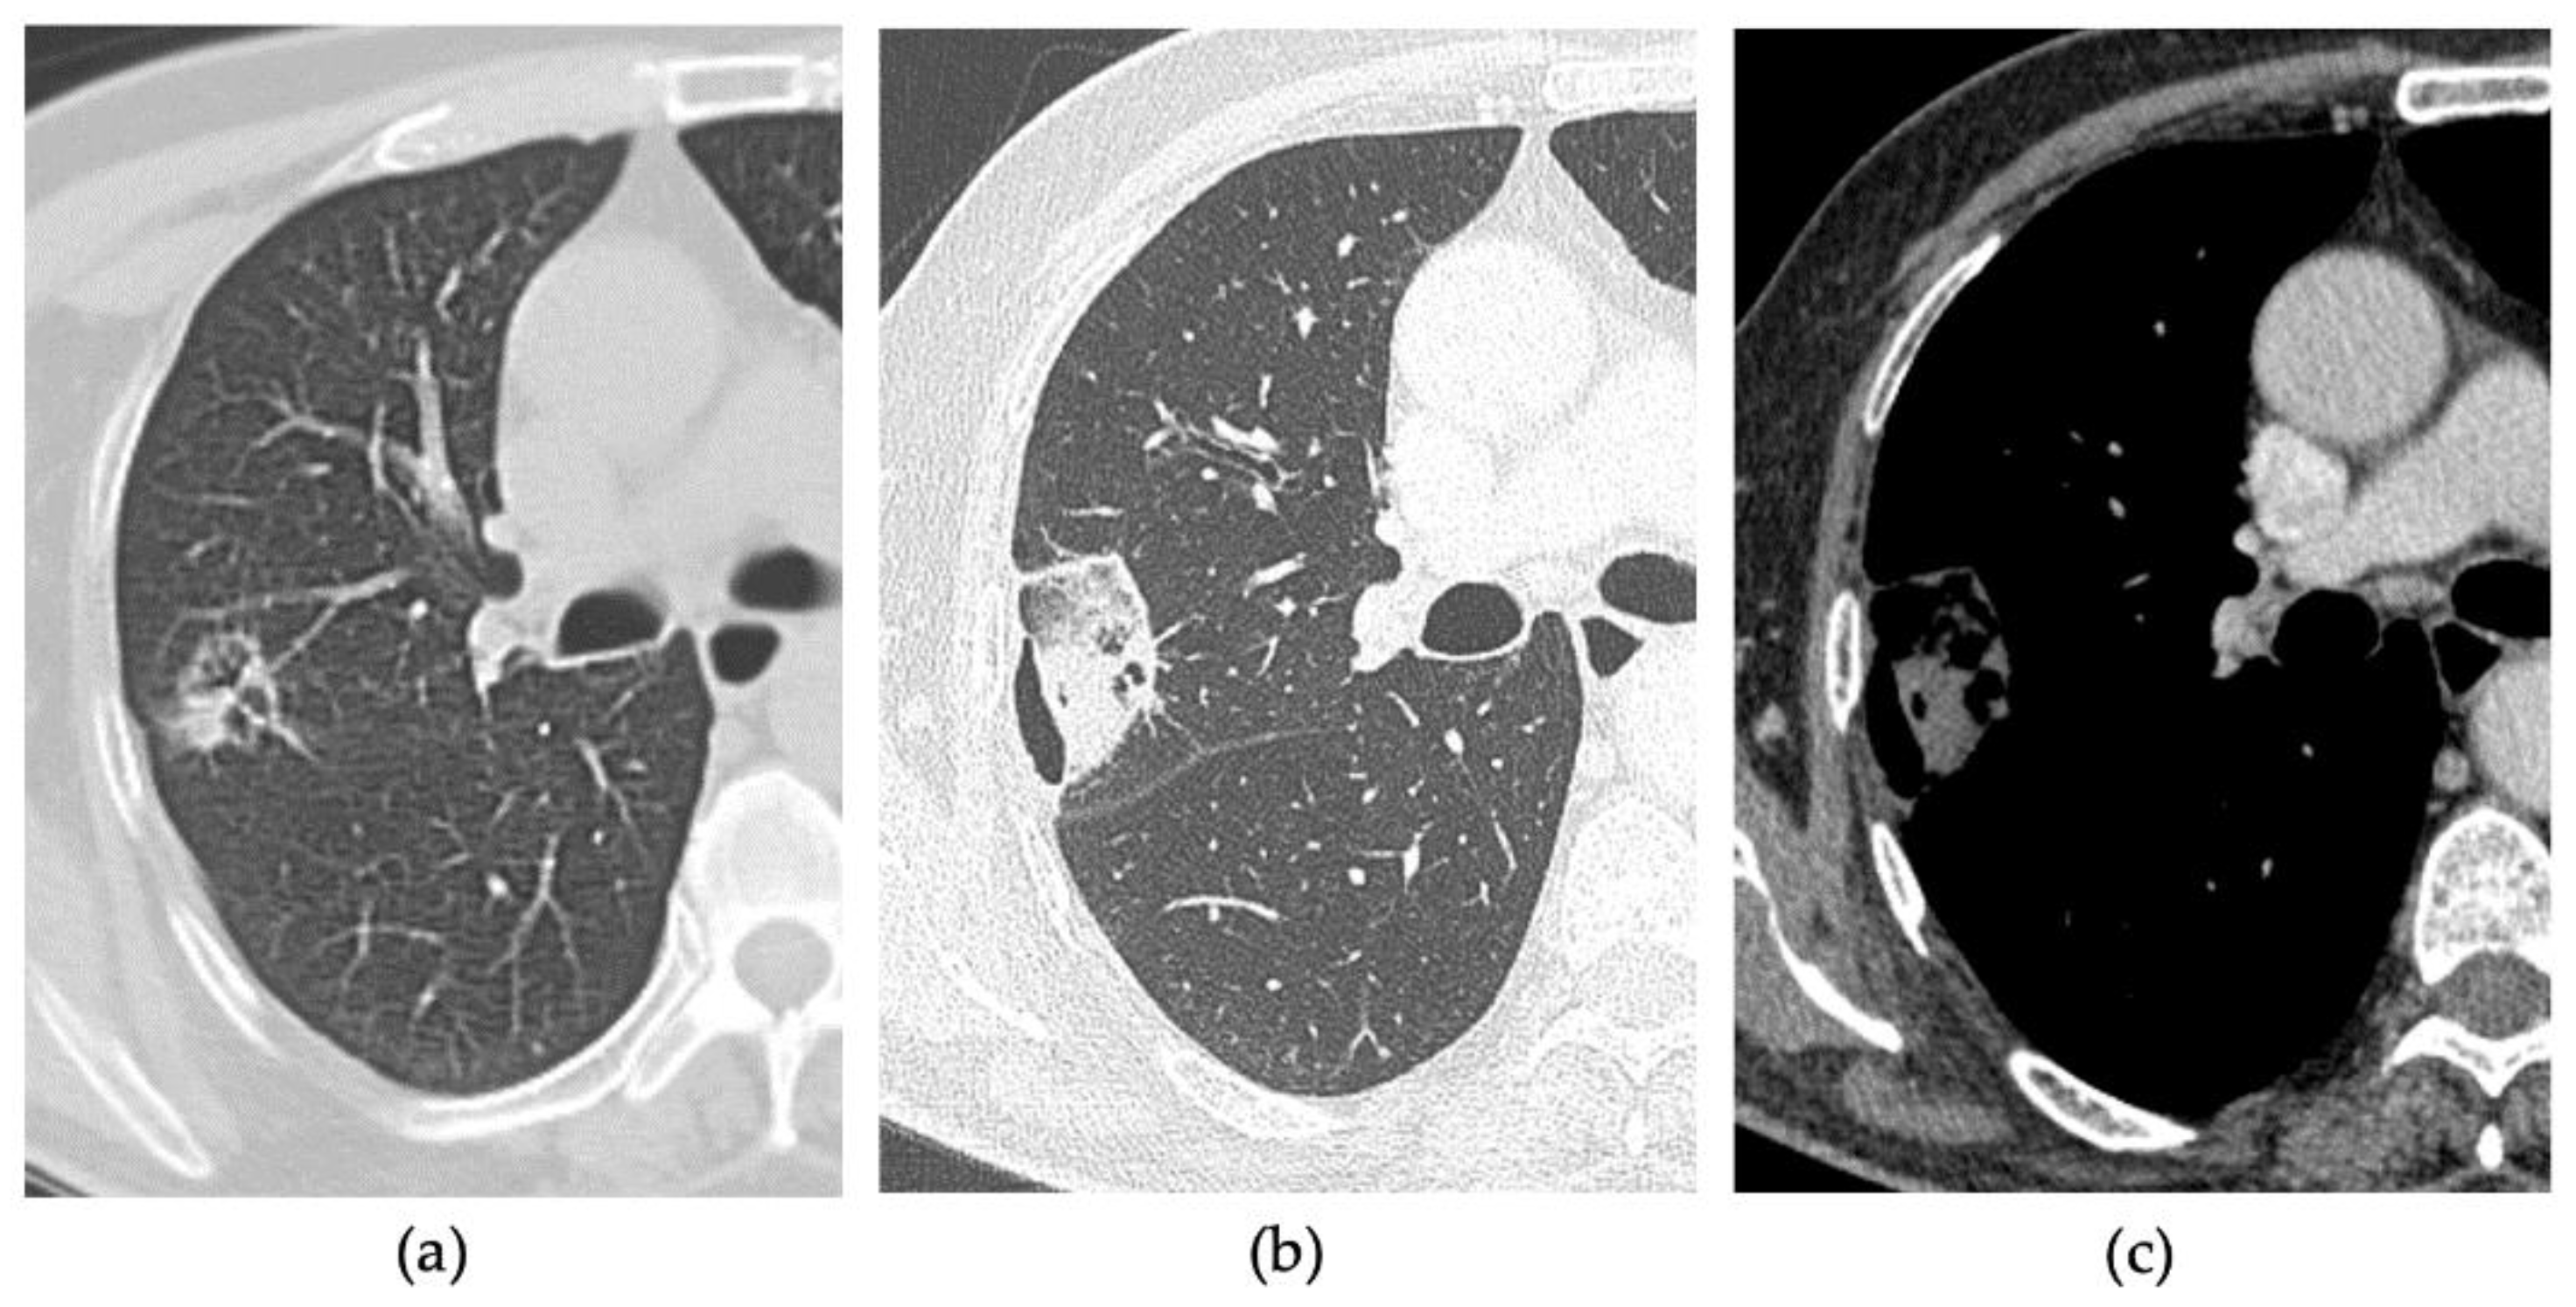

2.3. CT Follow-Up

3.3. Early Complications

3.3.1. Group 1

3.3.2. Group 2